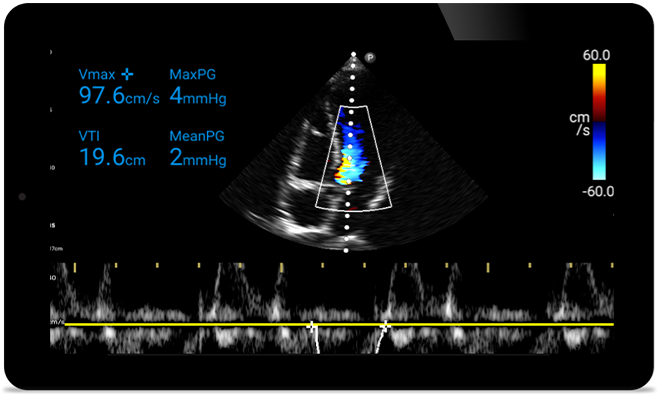

Actúe más rápido para proteger el corazón de sus pacientes

Cuando los segundos cuentan, el ultrasonido portátil puede marcar la diferencia. Lumify puede proporcionar las imágenes de alta definición que requiere cuando y donde las necesite.

Oportunidad de revertir potencialmente la miocardiopatía

Introducción a la ecocardiografía transtorácica